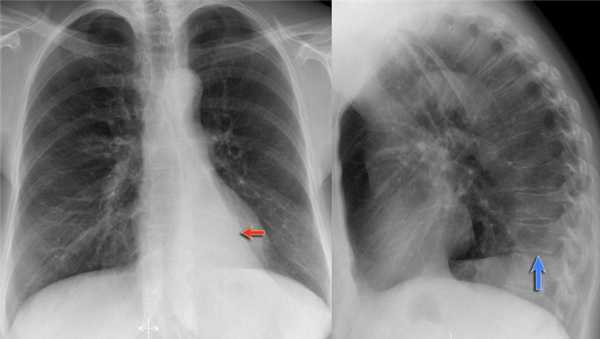

Ателектаз нижней доли левого легкого

На рентгенограмме визуализируются изменения трехгранной формы высокой плотности, расположенные позади тени сердца, что хорошо выявляется на боковом снимке. На боковом снимке при оценке контура диафрагмы спереди назад определяется все менее четко. Исходя из названия раздела напрашивается диагноз — ателектаз нижней доли левого легкого. В норме прозрачность легкого внизу выше, а в нашем случае наоборот (синяя стрелка).

Обратите внимание на правую междолевую артерию (красная стрелка) и границы правых отделов сердца (синяя стрелка).